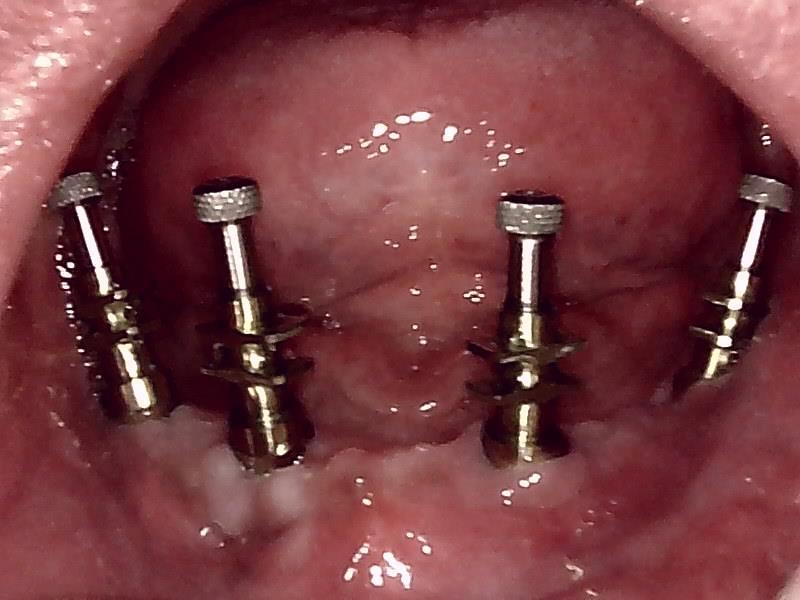

グラフト処置してから適時経過後、顎堤部の骨の厚みを担保したのち、

インプラント体の埋入します。(縫合時)

上部構造を精密印象して作成するため

歯軸の固定位置関係を精密に計測して作成していきます。